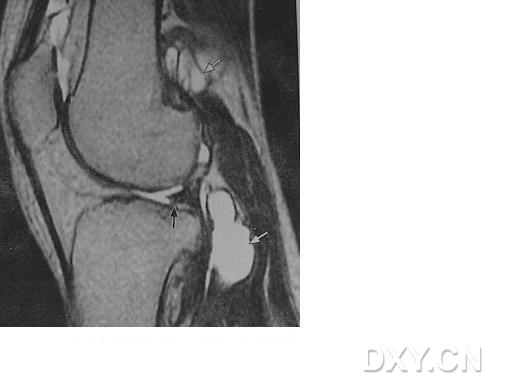

| 半月板囊肿 外侧半月板前角前缘1cm大小囊肿,合并外侧半月板前角的水平撕裂

|